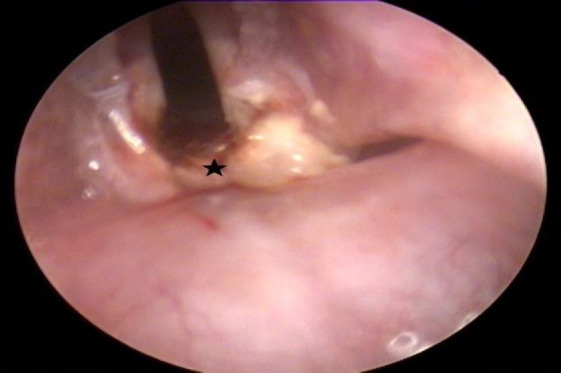

Materials and methods: Ten rabbits were included in this experimental study. A thermal injury was created at the posterior commissure using a conchal probe. Following the injury, one group was treated with mitomycin-C, while the other received epirubicin. After a six-week post-treatment period, the rabbits were euthanized, and both macroscopic and microscopic evaluations were performed to assess stenosis, scarring, granulation tissue, necrosis, and ulceration. Two pathologists, blinded to the treatment groups, independently examined the histological samples.

Results: Macroscopically, no significant differences were observed between the two groups in terms of scarring, synechiae, or granulation tissue formation at the posterior commissure. However, the mitomycin-C group demonstrated a relatively milder tissue response. Microscopic analysis revealed grade 3 collagen deposition in one rabbit and grade 1 in two rabbits from the epirubicin group. In comparison, the mitomycin-C group showed grade 1 deposition in two rabbits and grade 2 in another two. The average fibroblast count was 83.3 in the epirubicin group versus 59 in the mitomycin-C group.